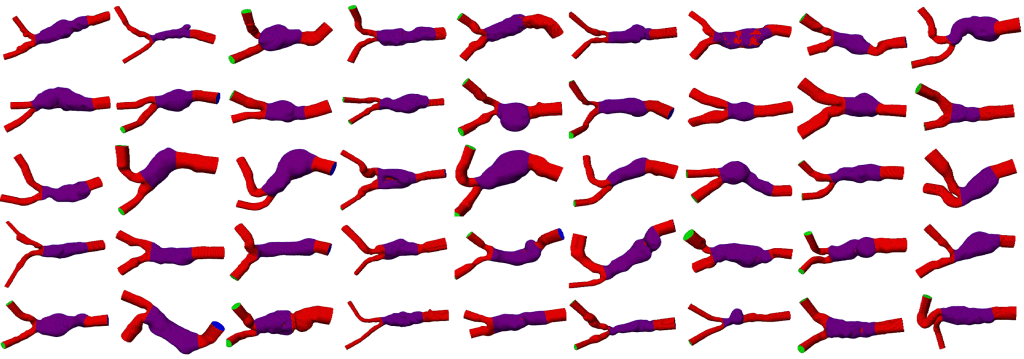

Deep Learning gestützte Extraktion anatomischer Strukturen für Patient*innen-Kohorten am Beispiel von abdominalen Aortenaneurysmen.

Mit der biomechanischen Simulation bildet das Team Abläufe im menschlichen Organismus nach – beispielsweise den Blutfluss. Dafür nutzt es segmentierte Bilddaten, erstellt Rechengitter (Meshes) und berechnet Materialeigenschaften wie Elastizität oder Viskosität. Auf dieser Basis können Ärzt*innen sowohl geometrische als auch simulationsbasierte Merkmale bestimmen. Dazu zählen etwa Gefäßdurchmesser oder mechanische Spannungen in Gefäßwänden.

Diese Ergebnisse erleichtern Diagnosen und Behandlungsentscheidungen. Zum Beispiel lässt sich das Rupturrisiko eines Aneurysmas berechnen oder die Wirksamkeit von Eingriffen im Blutgefäßsystem beurteilen. Außerdem finden die Modelle in medizinischen Simulatoren Anwendung, um Eingriffe realitätsnah zu trainieren.

Rupturrisiko von Aneurysmen

Aneurysmen werden in CTA-Scans (Computertomographie-Angiographie) diagnostiziert. Die Segmentierung von Aneurysmen und Blutgefäßen wird für die Erstellung eines Volumenmodells (Mesh) zur Blutflusssimulation verwendet. Die Simulation ermöglicht die Berechnung von Druck und Gefäßspannung. Für eine Patient*innen-Kohorte (z.B. Aneurysmenpatient*innen der letzten zehn Jahre) können diese Merkmale genutzt werden, um anhand von Machine Learning basierter Datenanalyse das Rupturrisiko zu ermitteln und darauf aufbauend eine geeignete Behandlungsstrategie zu wählen.